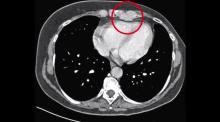

A 52-year-old patient was admitted to the authors’ department for left internal mammary artery lymph nodal metastases from breast cancer. The patient had undergone a left radical mastectomy 20 years earlier for breast cancer, and redo soft tissue excision 4 years after for isolated local recurrence. She then received chemo and hormone therapy, as well as radiotherapy. Prolonged follow-up disclosed a left internal mammary artery single site recurrence histologically proven by CT-guided needle biopsy.

Considering that the two lymph nodes of the internal mammary artery were the only site of recurrence of a very slow relapsing disease, oncologists recommended a lymphadenectomy. The authors planned a left videothoracoscopic lymphadenectomy of the involved lymph nodes of the internal mammary artery.